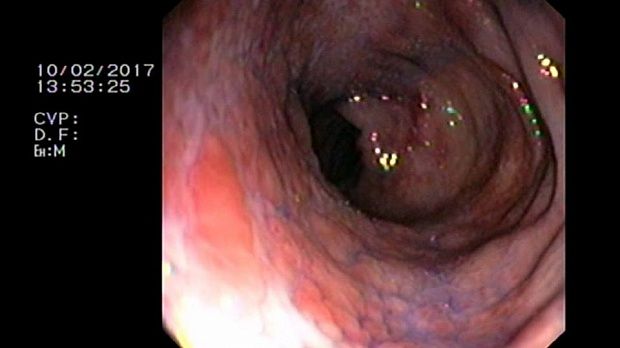

2 мл ( это мин сум, а мы делаем до 10 мл 3% перекись+200 мл физ раствора